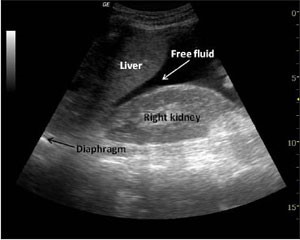

Focused Abdominal Sonography in Trauma: FAST-PGY III